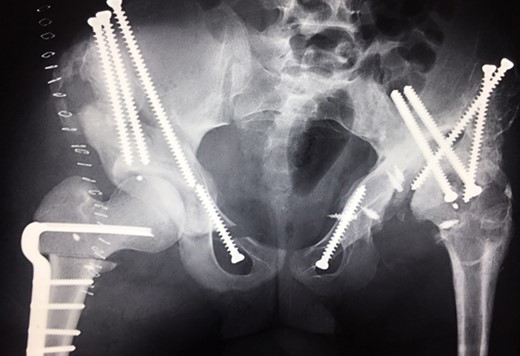

(2009) Operative reconstruction of the right hip with open reduction, capsular reconstruction with trevira tube augmentation, triple osteotomy and DVO of the proximal femur to prevent destructive degeneration was performed.

Ten years ago, a 12-year-old male presented to our clinic complaining about limping and massive swelling of the left hip. Figure 1 shows the initial X-ray and the 3D reconstruction of the left hip at first presentation when the femoral head, had already destroyed the lateral edge of the acetabulum like a mortar. Severe pain episodes have apparently not been noticed and a former hip dysplasia was not known. A brief clinical history revealed that the patient presented repeated episodes of finger biting and fevers from 2 to 8 years old. The intelligence level of the patient was at an average. The patient was admitted to a paediatric neurologist and a genetic test. A mutation of the NTRK1 gene was found and the diagnosis of CIPA was established. The right hip initially appeared to be normal and the patient was walking, therefore surgical reconstruction for the left hip was proposed due to massive swelling, inability of normal walking and significant limb length discrepancy. A Tönnis/Kalchschmidt triple pelvic osteotomy with open reduction and a shortening varus derotation osteotomy (VDRO) of the femur was performed (Fig. 2A–B). After 3 months the patient was walking again but another 3 months later the hip dislocated again without severe pain. Although the femoral head was already damaged the hip joint was reconstructed again by open reduction, capsular reconstruction with suture anchors and a trevira tube and a movable external fixator was used to temporary stabilize the joint (Fig. 3). The right hip at this time was still intact and was protected with a pneumatic orthotic device. A few months later in 2009, despite all surgeries, the left hip had entirely lost congruency and the right hip developed subluxation despite conservative treatment (Fig. 4). The patient was still walking so the decision to reconstruct the right hip with open reduction, capsular augmentation with a trevira tube, a triple pelvic osteotomy and VDRO was made (Fig. 5). Few months later this reconstruction failed as well and the hip dislocated without severe pain (Fig. 6).